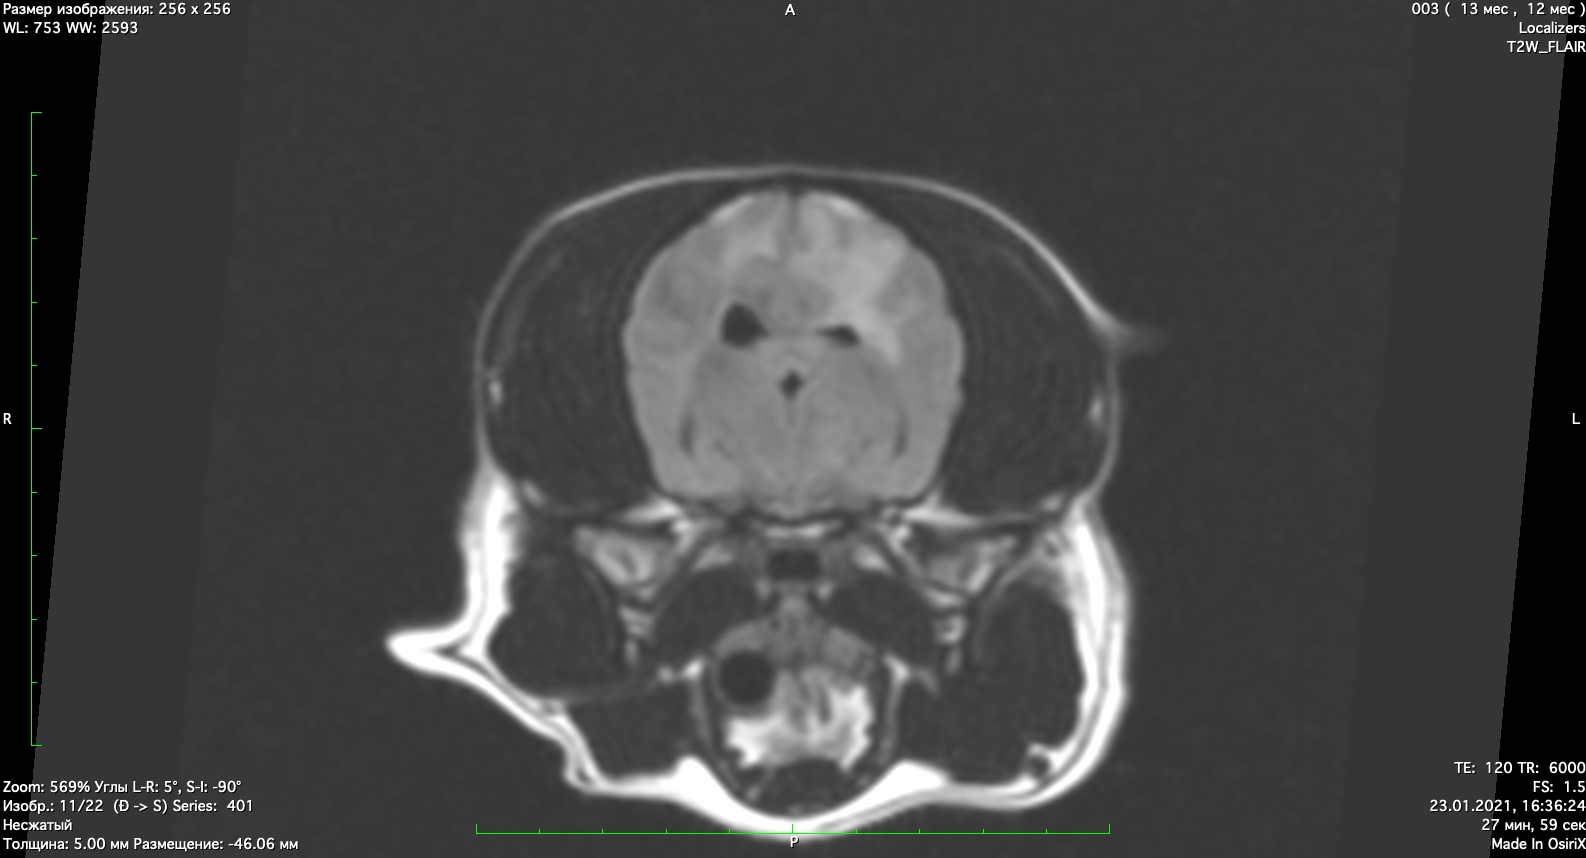

При проведении мрт диагностики установлено признаки мультифокального поражения головного мозга поставлен диагноз гранулематозный менингоэнцефалит неизвестной этиологии. Начато иммуносупрессивное лечение